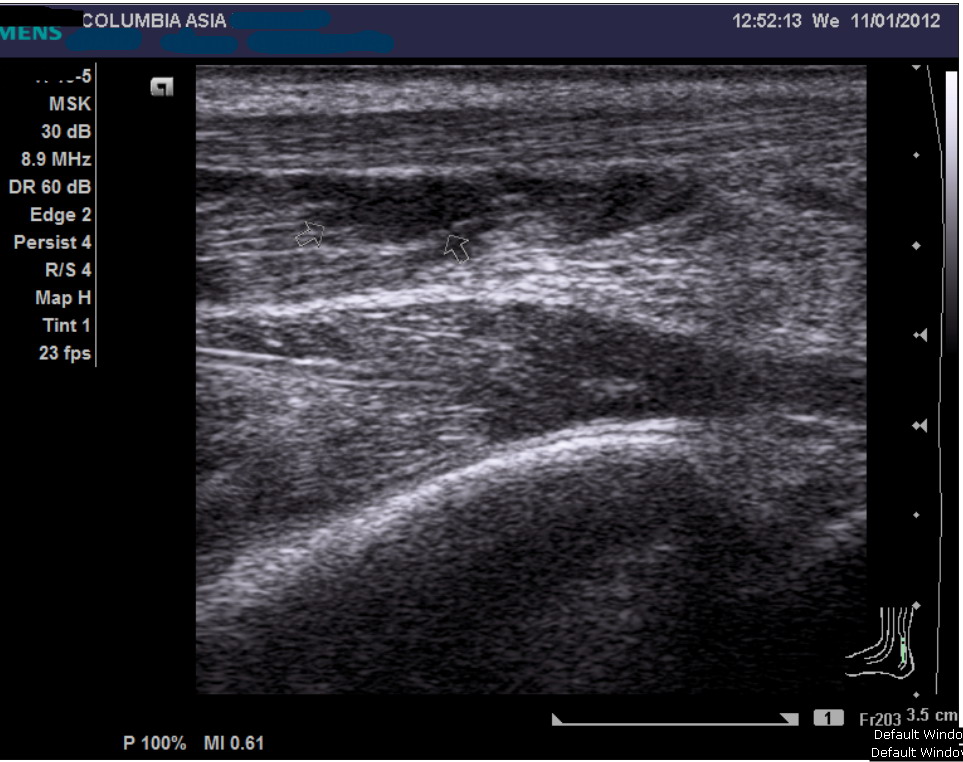

Gastrocnemius Tear Ultrasound Calf Muscle Gastrocnemius Tear A gastrocnemius rupture can be diagnosed clinically and involves a proximal calf injury after a sudden push. Gastrocnemius rupture is a common injury characterized by the tearing of the gastrocnemius muscle in the calf. A gastrocnemius muscle tear is caused by a severe, sudden injury to your calf muscle. A calf strain is a tearing injury to the gastrocnemius or. Calf Muscle Gastrocnemius Tear.

Gastrocnemius Tear Ultrasound Calf Muscle Gastrocnemius Tear The ankle) are also sometimes seen in clinical practise. A gastrocnemius muscle tear is caused by a severe, sudden injury to your calf muscle. A calf strain is a tearing injury to the gastrocnemius or soleus muscle. Gastrocnemius rupture is a common injury characterized by the tearing of the gastrocnemius muscle in the calf. A gastrocnemius rupture can be diagnosed. Calf Muscle Gastrocnemius Tear.

Gastrocnemius Tear Ultrasound Calf Muscle Gastrocnemius Tear The majority of calf strains are grade 2 tears and most commonly affect the gastrocnemius muscle (particularly the inner aspect i.e. Soleus strains although less common (due to the fact that the muscle only crosses one joint i.e. The ankle) are also sometimes seen in clinical practise. This part of the muscle is on the inner side of the back. Calf Muscle Gastrocnemius Tear.

Gastrocnemius Tear Ultrasound Calf Muscle Gastrocnemius Tear Gastrocnemius rupture is a common injury characterized by the tearing of the gastrocnemius muscle in the calf. A gastrocnemius rupture can be diagnosed clinically and involves a proximal calf injury after a sudden push. Soleus strains although less common (due to the fact that the muscle only crosses one joint i.e. The majority of calf strains are grade 2 tears. Calf Muscle Gastrocnemius Tear.

Gastrocnemius Tear Ultrasound Calf Muscle Gastrocnemius Tear The ankle) are also sometimes seen in clinical practise. Most often, the injury occurs in the medial gastrocnemius. By far the most common muscle involved in calf tears is the gastrocnemius, and the most common place that you would feel the strain is the middle inside section, halfway up, on the inside of the. This part of the muscle is. Calf Muscle Gastrocnemius Tear.

Gastrocnemius Tear Ultrasound Calf Muscle Gastrocnemius Tear This part of the muscle is on the inner side of the back of your leg. Most often, the injury occurs in the medial gastrocnemius. A gastrocnemius muscle tear is caused by a severe, sudden injury to your calf muscle. This muscle helps flex the lower leg. A calf strain is a tearing injury to the gastrocnemius or soleus muscle.. Calf Muscle Gastrocnemius Tear.

Calf Strain Medial Head of the Gastrocnemius Partial Tear! Radiology Calf Muscle Gastrocnemius Tear [6] [7] plantarflexion provides the propelling force during gait. Gastrocnemius rupture is a common injury characterized by the tearing of the gastrocnemius muscle in the calf. A gastrocnemius rupture can be diagnosed clinically and involves a proximal calf injury after a sudden push. Soleus strains although less common (due to the fact that the muscle only crosses one joint i.e.. Calf Muscle Gastrocnemius Tear.